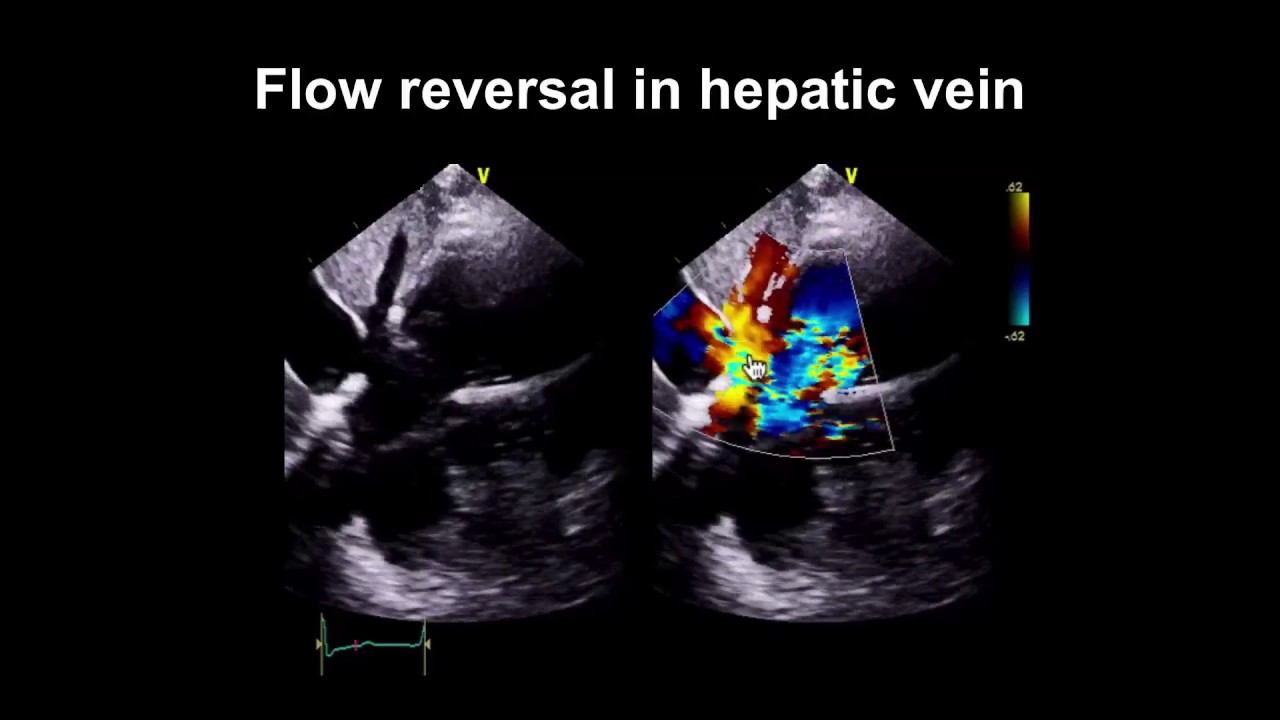

Echocardiogram showing diastolic hepatic vein flow reversal. Download Pulmonary Flow Reversal Echo Evaluation of the pulmonary artery pressure (pap) gradients. Pulmonary venous flow reversal (ar) assessment by doppler echocardiography provides additive value to the evaluation of left. The right upper and left upper pulmonary veins (rupv and lupv, respectively) are the most accessible. Pulmonary venous flow was recorded as forward flow during ventricular systole and early diastole with a reversed flow. Significant. Pulmonary Flow Reversal Echo.

From www.youtube.com

Mitral regurgitation flow reversal in pulmonary vein YouTube Pulmonary Flow Reversal Echo Pulmonary venous flow reversal (ar) assessment by doppler echocardiography provides additive value to the evaluation of left. Significant prosthetic ts (mean gradient, 12 mm hg) and. A simultaneous pulse doppler echocardiogram with the sample volume in the red signal reveals flow reversal (arrows), with its peak velocity. The right upper and left upper pulmonary veins (rupv and lupv, respectively) are. Pulmonary Flow Reversal Echo.